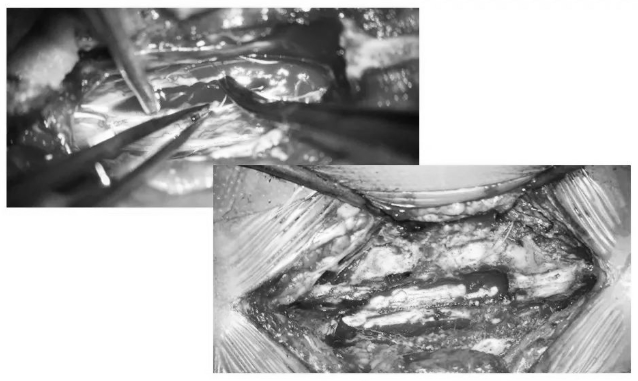

▼沿后正中切开,即可见含铁血黄素沉积带及陈旧性血凝块

▼用细致的双较或者剥离子沿含铁血黄素沉积带,分离海绵状血管瘤并电凝切断供血分支血管

▼逐步显露血管瘤腹侧面

▼血管瘤完整取出

▼用Proline缝线间断缝合软脊膜,封闭瘤腔,水密缝合硬脊膜